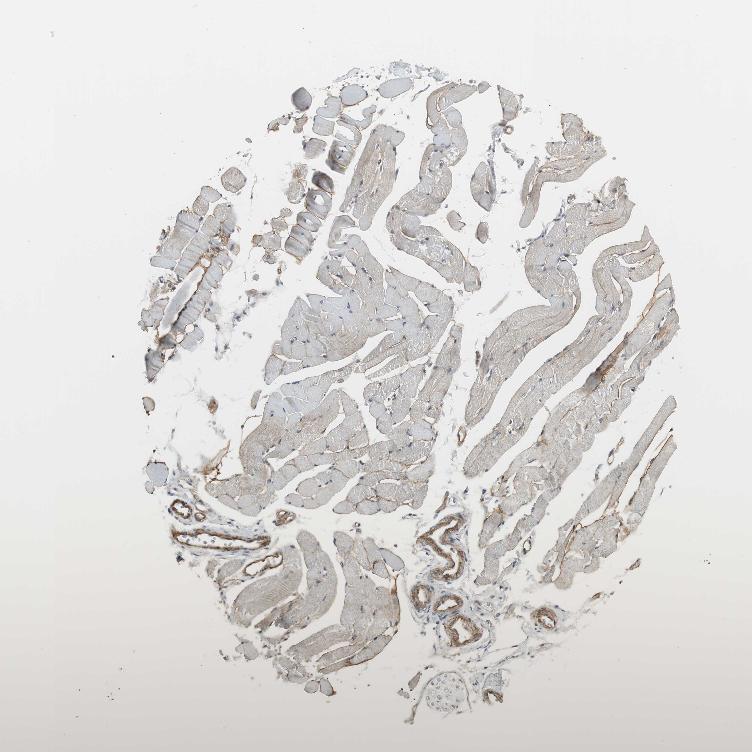

SKELETAL MUSCLE - Antibody stainingi

Antibody staining in the annotated cell types in the current human tissue is reported as not detected, low, medium, or high, based on conventional immunohistochemistry profiling in selected tissues. This score is based on the combination of the staining intensity and fraction of stained cells.

Each image is clickable and will lead to virtual microscopy that enables deeper exploration of all samples and also displays staining intensity scores, fraction scores and subcellular localization as well as patient and tissue information for each sample.

Antibody HPA005624

Myocytes Not detected